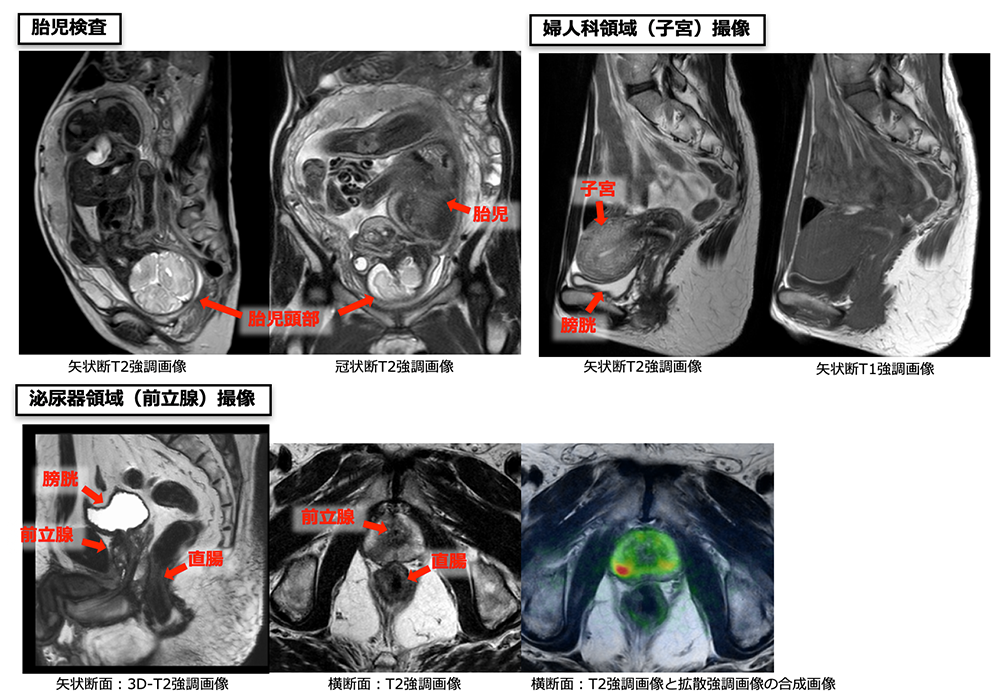

婦人科領域である子宮や卵巣、泌尿器領域の前立腺、膀胱、精巣、消化管領域の直腸、肛門など幅広く撮像を行っています。また、妊娠中の患者さんを撮像することで、胎児の状態や胎盤の評価なども行うことができます。